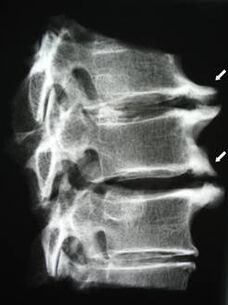

W początkowych stadiach osteochondrozę wykrywa się za pomocą MRI. Później patologię można zdiagnozować za pomocą radiografii. Na radiogramach kręgosłupa szyjnego zauważalne jest zmniejszenie odległości między kręgami, zmiany patologiczne w stawach międzywyrostkowych i osteofitoza.